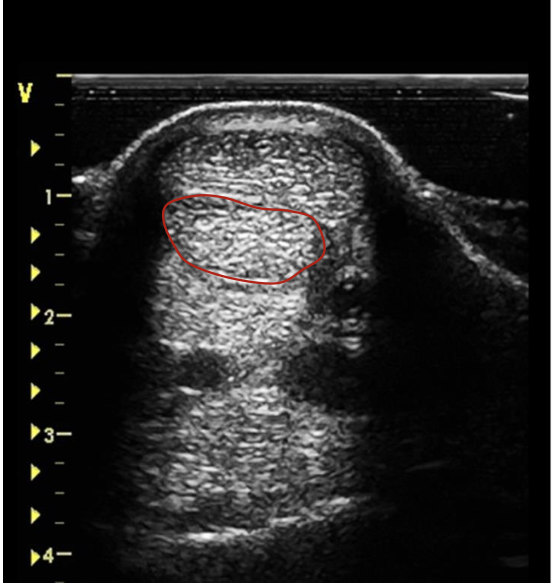

what are the portions of the suspensory ligament on a transverse scan?

proximal origin

body

lateral and medial branches

how does the suspensory ligament appear in younger horses?

mottled, hypoechoic appearance

how is the suspensory ligament appearing at every portion?

bilaterally symmetrical at any level

how does the suspensory ligament appear at the origin and body on transverse scan?

rectangular in cross-section

body is coarser, more heterogenous, and less echogenic than tendons